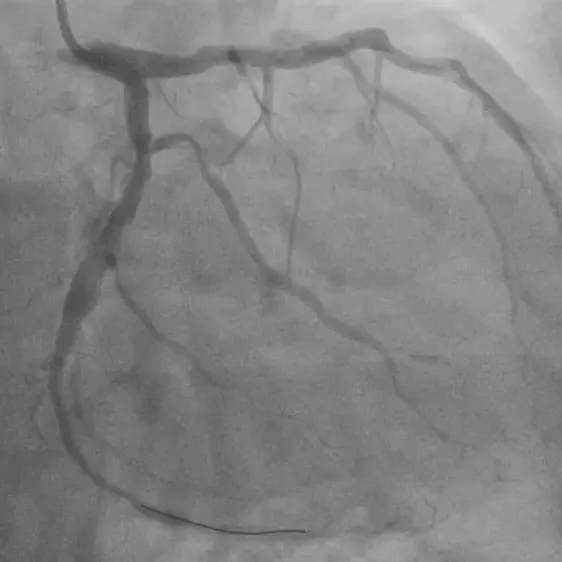

首例患者为一名患有冠心病的52岁男性,经术前冠脉造影检查显示左冠前降支和回旋支均有80%以上狭窄病变,需进行支架植入治疗,在与患者充分沟通并签署知情同意书后,手术顺利实施。

基线造影—左冠回旋支

术后即刻造影显示,支架扩张、贴壁良好无残余狭窄,TIMI血流3级,手术效果显著。

术后造影—左冠前降支

术后造影—左冠回旋支